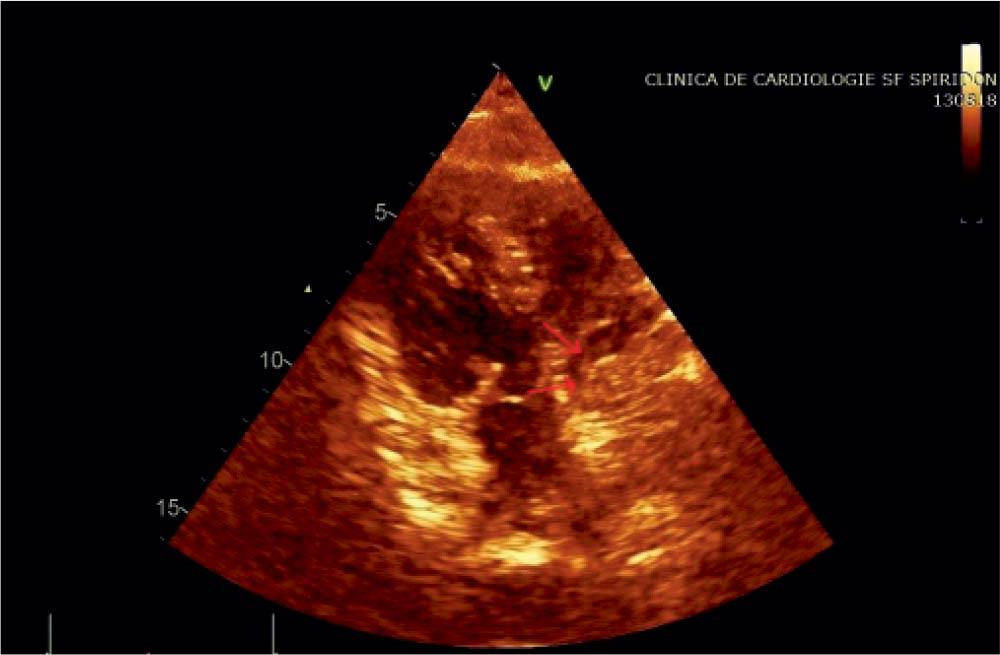

Figure 2

Transthoracic echocardiography right apical 4C view (poor accuracy due to dextrocardia): mass filling almost entirely the right atrium; LV hypertrophy.